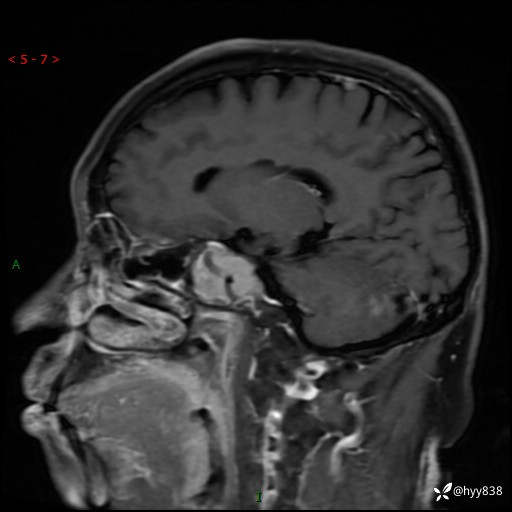

现病史:患者半年前无明显诱因出现头痛头痛,呈间断性发作,无复视,无斜视,无头痛头晕,无呕心呕吐,无肢体乏力,无发作性肢体抽搐,无意识改变,无尿量增多,无体毛脱落,无色素沉着,无体重下降,无面容改变,无肢端粗大等,2024-03-26日至当地中医院住院治疗后予以对症处理(具体不详),未见明显缓解,行头颅MRI平扫检查示:“右侧蝶鞍占位,双侧上颌窦炎,双侧下鼻甲肥大,鼻中隔偏曲”,今患者为求进一步诊治来我院,门诊遂以“右侧蝶鞍占位”收住我科。 起病以来,患者精神饮食睡眠可,大小便正常。

MRI增强(外院平扫)